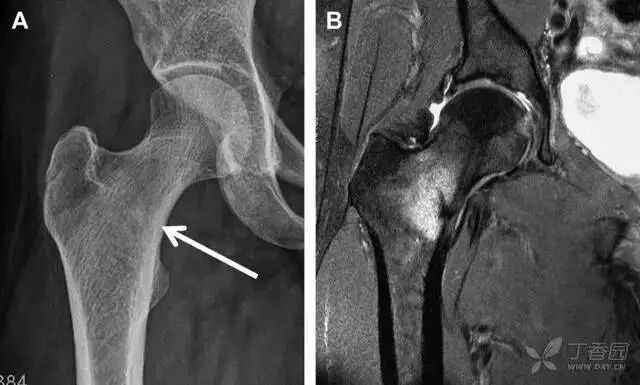

04股骨头骨折

股骨头骨折常与髋关节脱位有关。需要注意的是那些既不是因剪力损伤也不是因直接暴力作用造成的骨折。这些类型的骨折可能十分轻微。提倡应用 CT 检查,不仅可诊断骨折,而且能评估关节内骨折碎片的位置(图 6)。

图 6 股骨颈骨折伴髋关节脱位。A 股骨头上外侧轮廓缺失(空箭头)注意嵌入上方关节间隙的骨折碎片(黑色箭头)B 冠状位 CT 多维重建(MPR)证实骨软骨碎片(白色箭头)和关节上方的另一个碎片(空箭头)